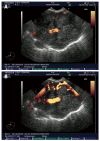

Contrast agents are increasingly being used to characterize the vasculature in an organ of interest, to better delineate benign from malignant pathology and to aid in staging and directing therapeutic procedures. We review the mechanisms of action of first, second and third generation contrast agents and their use in various endoscopic procedures in the gastrointestinal tract. Various applications of contrast-enhanced endoscopic ultrasonography include differentiating benign from malignant mediastinal lymphadenopathy, assessment of depth of invasion of esophageal, gastric and gall bladder cancers and visualization of the portal venous system and esophageal varices. In addition, contrast agents can be used to differentiate pancreatic lesions. The use of color Doppler further increases the ability to diagnose and differentiate various pancreatic malignancies. The sensitivity of power Doppler sonography to depict tumor neovascularization can be increased by contrast agents. Contrast-enhanced harmonic imaging is a useful aid in identifying the tumor vasculature and studying pancreatic microperfusion. In the future, these techniques could potentially be used to quantify tumor perfusion, to assess and monitor the efficacy of antiangiogenic agents, to assist targeted drug delivery and allow molecular imaging.